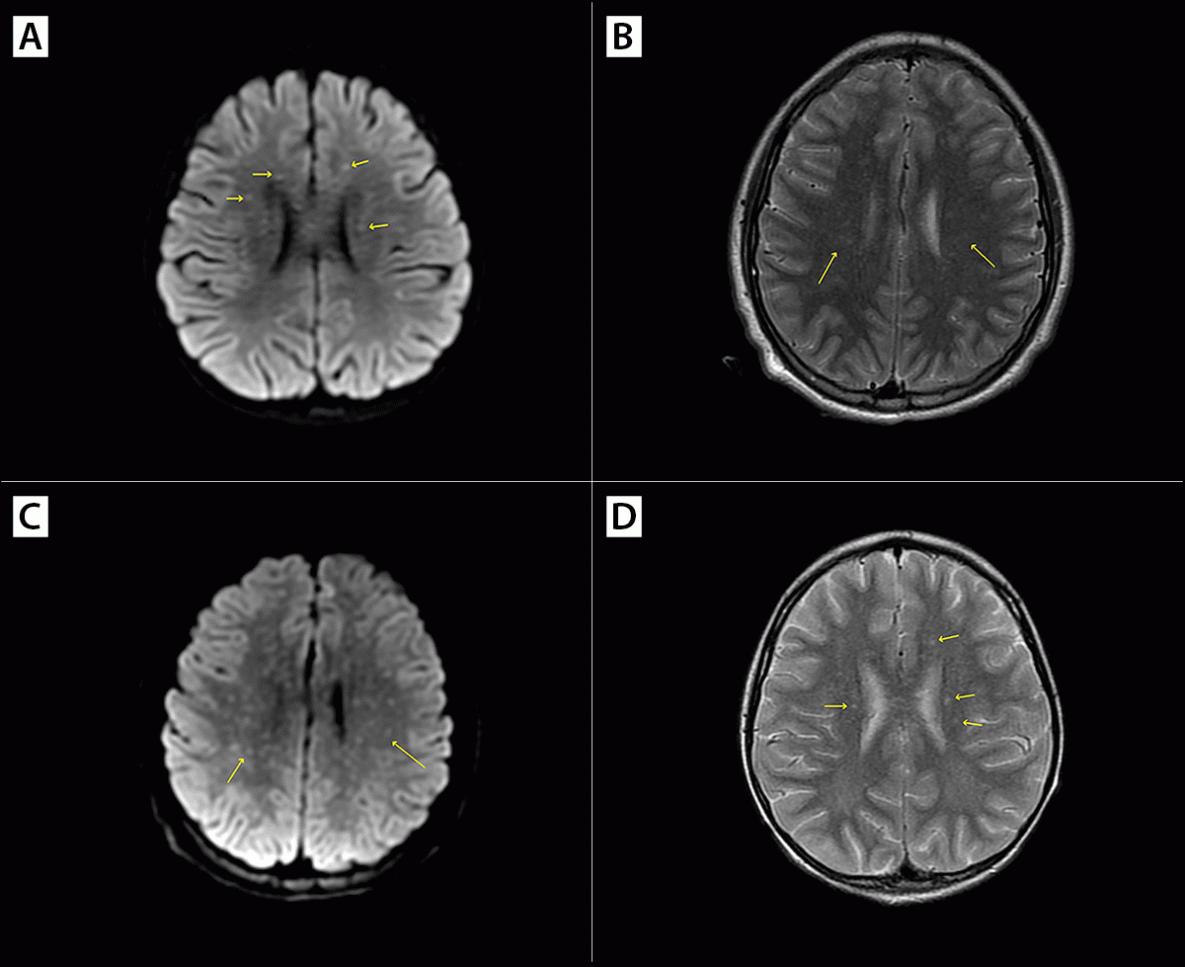

Patients B and C were siblings aged 4.5 and 3 years, respectively, who became ill on the same day in August 2023 in Tecate. A tick was removed from patient C at home 2 days before symptom onset; when the tick attached was not known. Both children developed a rash, initially thought to be varicella, 2 days after the tick was found and removed from patient C, and both became lethargic over the next 2 days. Patient B developed diarrhea and respiratory difficulty, and the rash on both children spread to involve the whole body. Health care was sought in California on the fifth day of illness; patient B succumbed to cardiac failure en route to the health care facility. RT-PCR testing of a postmortem blood specimen returned a positive result for R. rickettsii. FFPE tissue from multiple organs (skin, kidney, liver, spleen, thymus, testis, adrenal gland, and tongue) obtained at autopsy and evaluated at CDC’s Infectious Diseases Pathology Branch indicated extensive, predominantly small-vessel, vasculitis and abundant antigens of spotted fever group Rickettsia when stained using immunohistochemistry (IHC) (Figure 1). DNA extracts from IHC-reactive FFPE tissue blocks were positive for R. rickettsii by PCR. Patient C was taken to a tertiary care facility in San Diego, where treatment with doxycycline was started in the ED because of a high index of suspicion for RMSF; the diagnosis was confirmed 2 days later by a Karius Test positive for R. rickettsii mcf DNA. Patient C’s evaluation in San Diego included magnetic resonance imaging of the brain, which showed small foci of signal abnormality in the white matter (known as a “starry sky” appearance), a finding highly associated with RMSF (Figure 2).

Patient F, an adolescent boy aged 13 years, became ill with cough and fever in January 2024 while in Tecate. His family reported a small red bump on his arm 1 week earlier that developed into a dark scab. A rash appeared over a majority of his body 2 days later. Health care was sought at an ED in San Diego. He was started on doxycycline because of suspicion of RMSF. A magnetic resonance imaging of the brain demonstrated a small foci of signal abnormality in the white matter (Figure 2). After a 35-day hospitalization, he completed 2 weeks of rehabilitation before discharge.

FIGURE 2. Magnetic resonance imaging findings*,† for cases of Rocky Mountain spotted fever in two residents of Tecate, Mexico (a child aged 3 years [A and B] and an adolescent aged 13 years [C and D]) with small foci of signal abnormality in the white matter indicated (“starry sky” appearance)§ — California, August 2023

Photos/County of San Diego Health and Human Services Agency, San Diego, California

* Axial diffusion-weighted imaging, panels A and C.

† Axial T2-weighted imaging, panels B and D.

§ Multiple punctate foci of reduced diffusivity and edema, suggesting white matter ischemic foci associated with vasculitis.